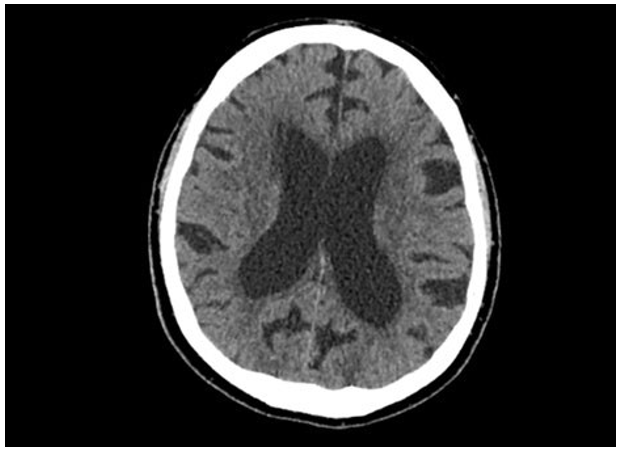

Ct Brain |

Normal |

Figure 2: CT brain showing no intracranial pathology or evidence of metastatic spread CT pulmonary angiogram (20/01/23): Dense consolidation right lower dorsal and basal segment. No pulmonary embolism identified. Metastatic bony changes with progression from previous scan in 5/10/22. Most of thoracic vertebra affected by bony disease. Metastatic deposits in sternum and ribs.